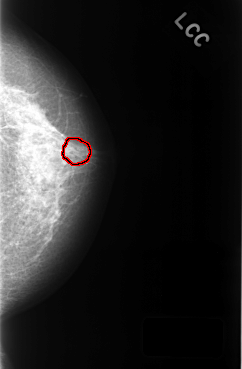

C_0320_1.LEFT_CC

FILE: C_0320_1.LEFT_CC.OVERLAY

TOTAL_ABNORMALITIES 1

ABNORMALITY 1

LESION_TYPE CALCIFICATION TYPE PUNCTATE DISTRIBUTION CLUSTERED

ASSESSMENT 4

SUBTLETY 3

PATHOLOGY BENIGN

TOTAL_OUTLINES 1

BOUNDARY